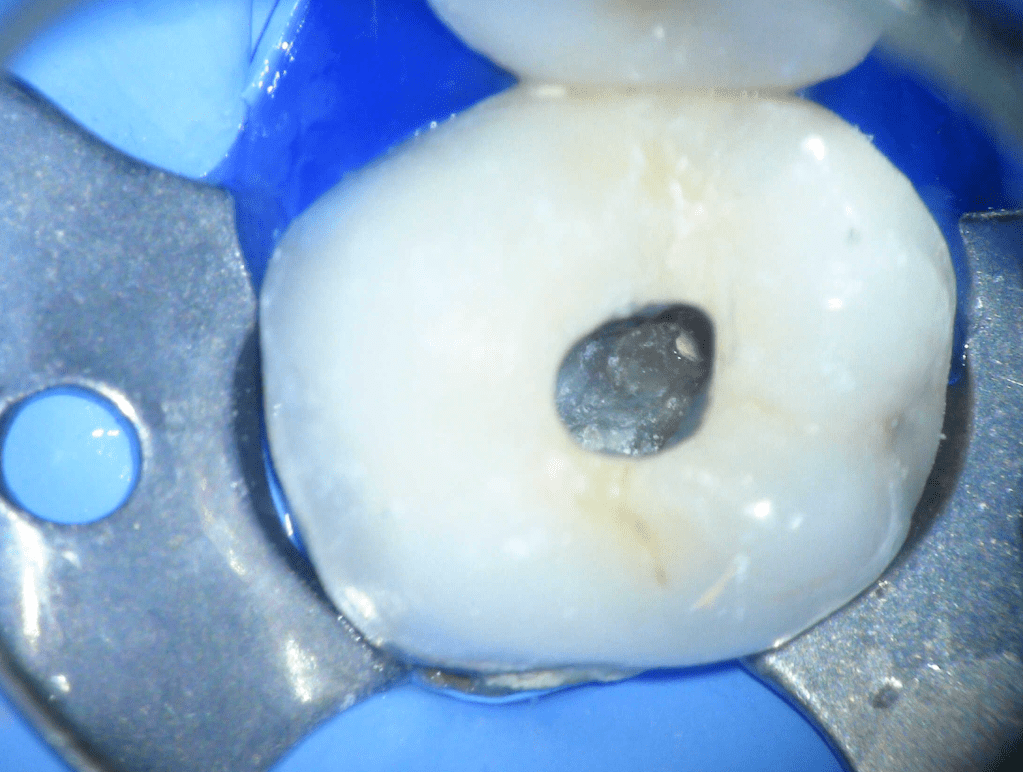

Pulpotomía biodentine + reco preendio